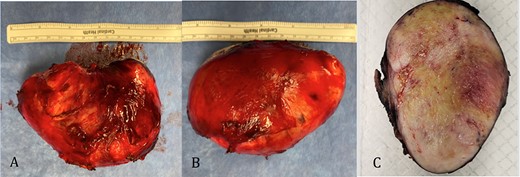

The pathology revealed a 282-g nodular tumor measuring 10.7 × 8.5 × 7 cm that was grossly tan, fibrotic and firm with focal yellow discoloration and soft flesh areas (Fig. 6). Microscopic analysis revealed high-grade spindle cell sarcoma arranged in intersecting fascicles with extensive areas of necrosis (Fig. 7). The lesional cells had fibrillary eosinophilic cytoplasm and evoid nuclei with nuclear pleomorphism (Fig. 8). Areas of rhabdomyoblastic and chondroid differentiation were also noted (Figs 9 and 10). Immunostaining was positive for desmin, focally for CD 34 and Bcl2, while Cam 5.2, CD117, S-100, SMA and HME45 immunostains show patchy staining for myogenin. Expression of H3K27me3 was completely lost in the tumor cells. MyoD1, SOX10, MDM2 and CDK4 were negative. It was identified as a high-grade MPNST with heterologous rhabdomyosarcomatous differentiation, i.e. MTT. All margins were negative.

Gross pathology: A and B. 282-g nodular tumor mass, measuring 10.7 × 8.5 × 7 cm. The external surface covered by tan, fibrous tissue. Attached irregular, fibrous tissue measuring 7 × 2.5 cm. C. Black ink was applied on the external surface. Cut surfaces are light tan, firm, fibrotic appearing with focal yellow discoloration and soft flesh areas.